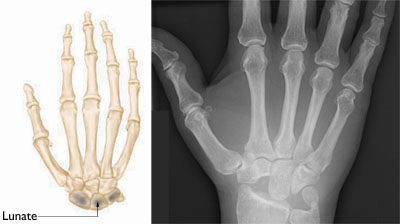

Normal skeletal anatomy of the hand.

Reproduced and modified with permission from JF Sarwark, ed: Essentials of Musculoskeletal Care, ed 4. Rosemont, IL, American Academy of Orthopaedic Surgeons, 2010.